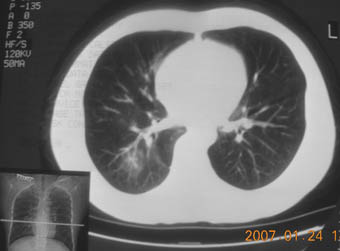

锁骨骨折复查,发现肺内高密度影,行ct检查。

男性,35岁,无任何感觉,无明显发热感冒病史。

病灶呈条片样变,边缘模糊,首先抗炎,然后复查。

病灶多形态:考虑结核可能性大

右肺下叶背段斑片状阴影,边缘模糊,纵隔内未见肿大淋巴结,病人无发热及感冒史,要考虑浸润型肺结核,可结合ppd检查,或短期抗炎治疗复查。

右肺下叶背段长椭圆型病灶,边缘较规则,无明显分叶征、毛刺,远段未见阻塞征象,病灶较松散,纵隔窗明显小于肺窗,年龄35岁,支气管稍示变窄,纵隔内未见明显肿大淋巴结,这些都不支持肿瘤。病人无任何感觉,无明显发热感冒病史,首先考虑结核(也是结核好发部位),慢性炎症不能完全除外。